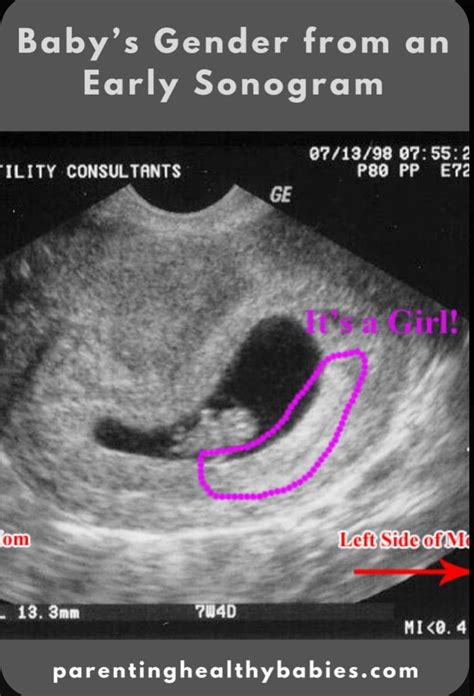

Ang gender ng baby ay maaaring malaman sa pamamagitan ng ultrasound sa pagitan ng 18 hanggang 20 na linggo ng pagbubuntis. Maaari din itong malaman sa pamamagitan ng genetic testing.

Ang gender ng baby ay maaaring malaman sa pamamagitan ng ultrasound sa ika-20 linggo ng pagbubuntis. Gayunpaman, hindi ito 100% na tumpak dahil may mga pagkakataon na hindi nakikita ang kasarian ng sanggol sa ultrasound.